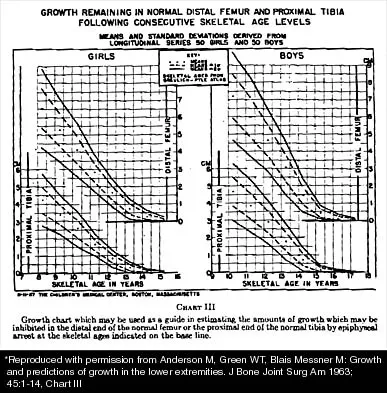

Question 35High Yield

A 10-year-old girl with a monoarticular pattern of juvenile rheumatoid arthritis (JRA) has had a 3-cm limb-length discrepancy since age 8 years when inflammation in the right knee came under good medical control. Because her right leg is longer, the patient states that she would like her legs to be close to equal in length in the future. A growth-remaining chart is shown in Figure 14. Management should consist of

Explanation